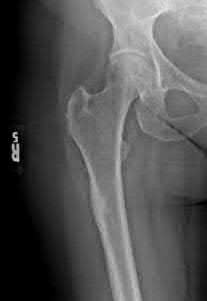

A 12-year-old obese boy presents with vague left thigh and knee pain. He is diagnosed with a Slipped Capital Femoral Epiphysis (SCFE) as seen in similar clinical scenarios.

During percutaneous in-situ fixation, unrecognized penetration of the guide wire into the hip joint occurs. What is the most likely specific complication resulting from this technical error?